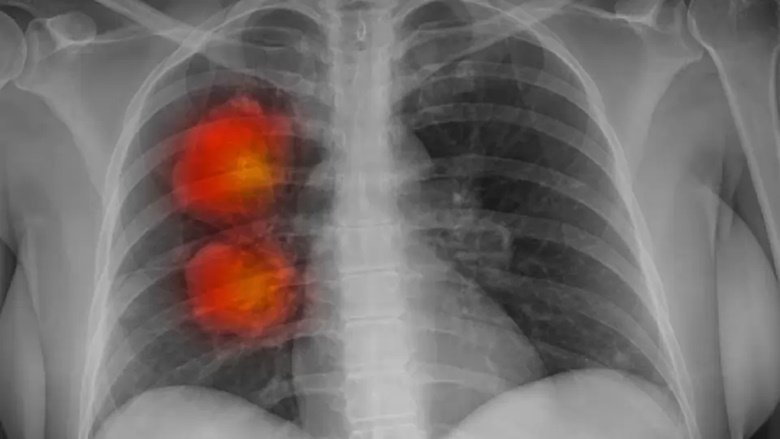

Recent research analyzing nearly 15,000 cancer cases across the UK found that over 17% of hard-to-treat tumors contain ecDNA fragments. These fragments fuel tumor growth and create resistance to standard treatments, posing a significant challenge in cancer therapy.